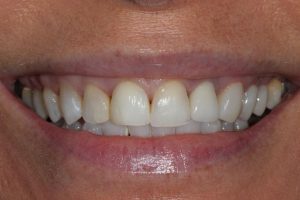

This patient had broken their upper front tooth and the exisitng dental crown had fallen off. The underlying root was unfortunatley irreparable.

The dental root was subsequently removed and an implant placed at the same time. The implant had a temporary crown placedon the same day.

The ‘After’ photos shows the final crown that was made after 3 months. The implant crown was made to match the form and colour of the exisiting teeth to give an overall natural aesthetic finish.